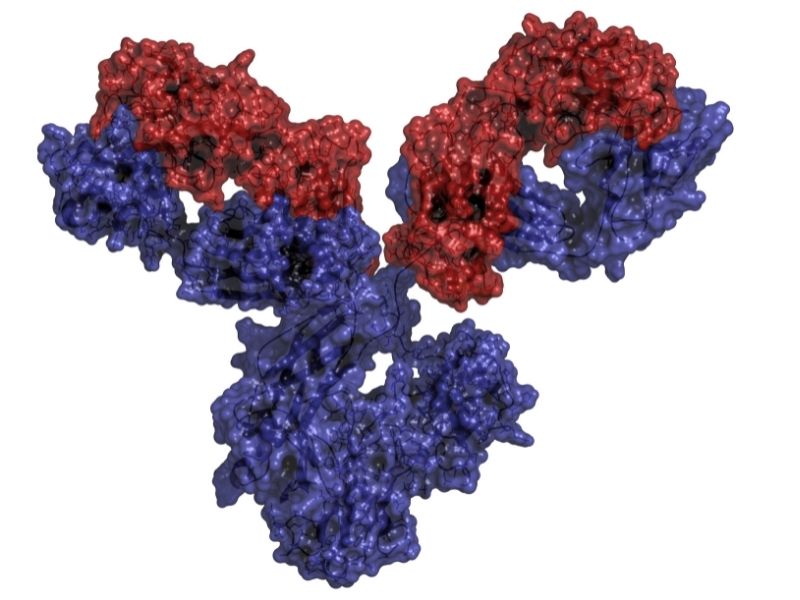

Oggi la ricerca è fortemente impegnata su due fronti:

- Individuare marcatori precoci, cioè segnali biologici che permettano di intercettare la malattia prima che si manifesti;

- Sviluppare terapie sempre più mirate ed efficaci, anche nei casi più avanzati.

Sono proprio queste le strade che possono rendere il tumore al polmone più curabile.